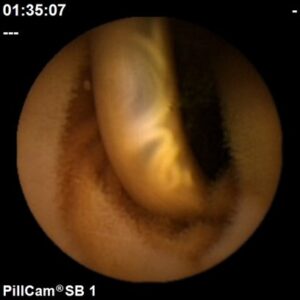

Angiectasia do intestino delgado

Hospital Senhora da Oliveira (Guimarães)